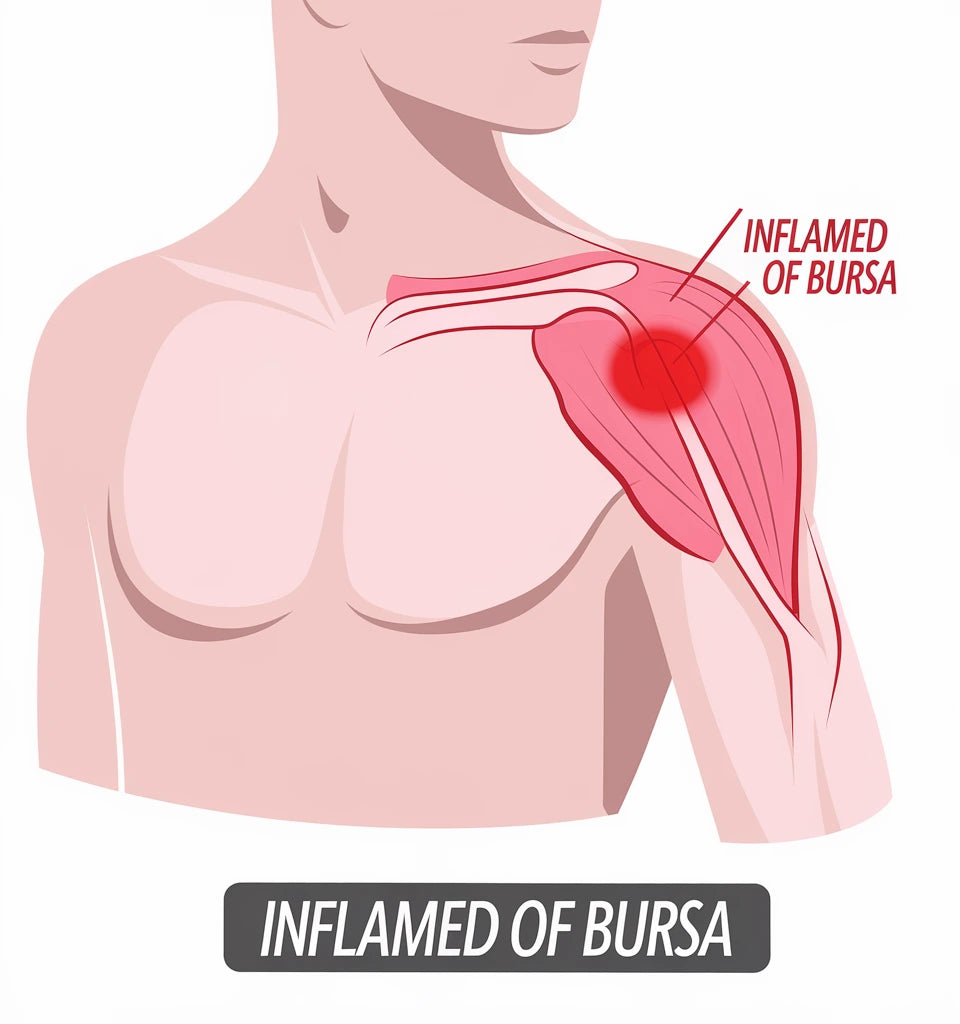

Axelleden är en av kroppens mest rörliga leder – men också en av de mest utsatta. Smärta i axeln kan bero på inflammation, överansträngning eller ledförslitning. Lär dig mer om olika axelproblem och hur du kan lindra dina symtom.